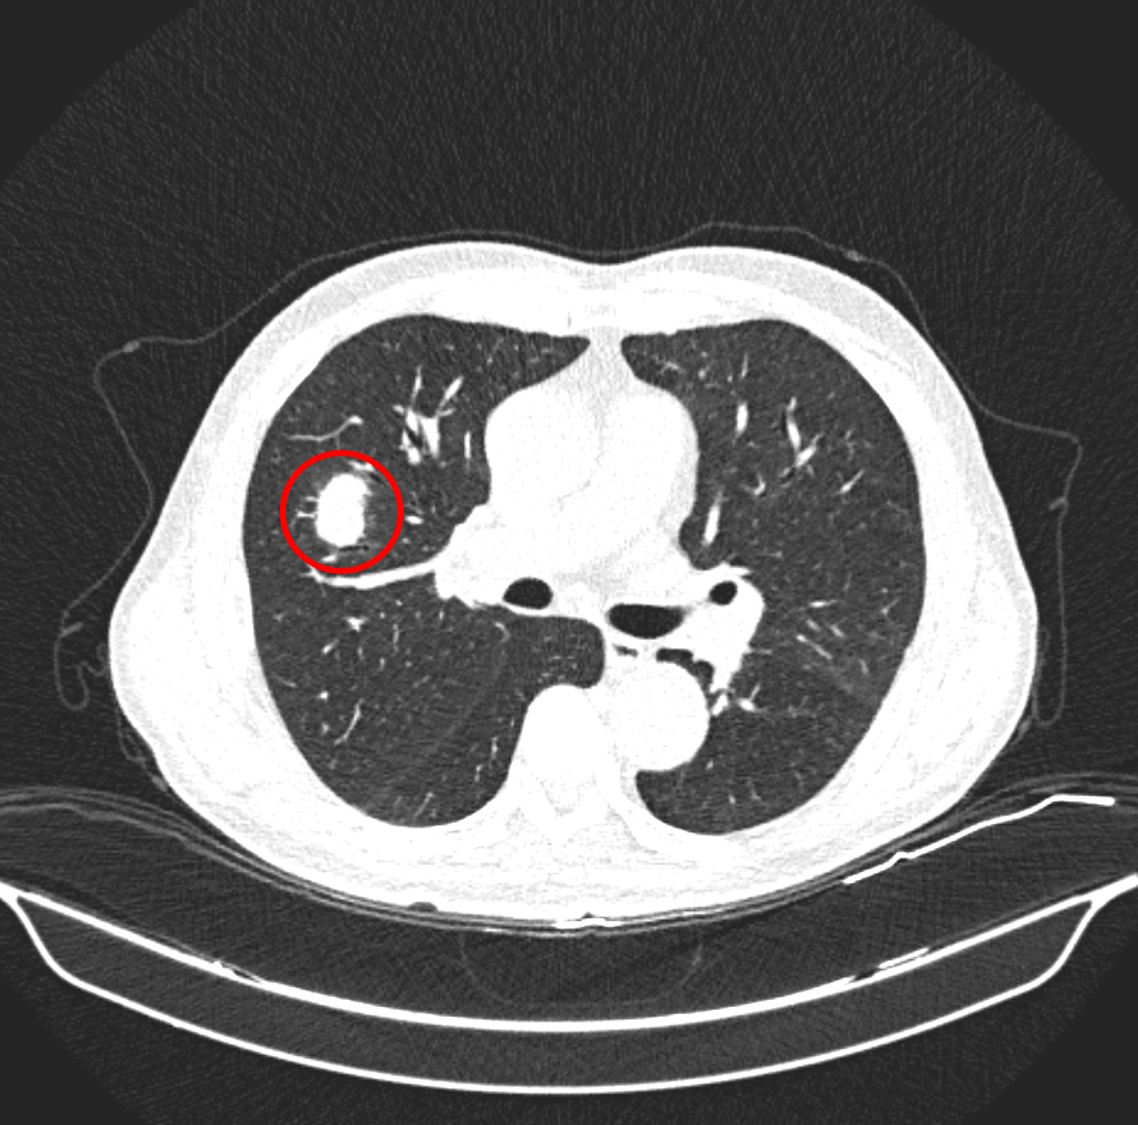

얼마나 환자를 보았을까, 잠시 숨 돌릴 여유가 생기자 김성훈 씨 CT를 확인했다. 2년 전에 6mm 크기의 결절이 2년 만에 3cm 가까이 자라 있었다. 판독은 나오지 않았지만, 폐암일 확률이 다분했다. 불행히도 김성훈 씨는 98~99%가 아니라, 1~2%에 속했다.

<2년 동안 커져버린 폐암, 4B>

김성훈 씨가 6개월에 폐 CT를 찍은 후, 진료를 받고 치료를 받았다면 생존율이 얼마나 올라갔을까? 폐암의 경우, 대략 1기 80%, 2기 60%, 3기 30%, 4기 10% 수준이다. 폐암을 막을 수는 없지만, 적어도 10~20% 이상 살 확률이 올라갔을 것이다.